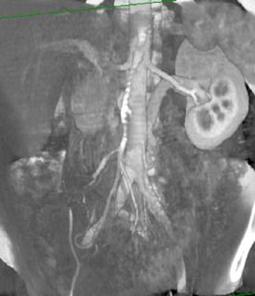

Imagini computertomografice ale vaselor renale: anatomia normala si variante anatomice

Aa.renale normale

Ramificare prehilara a aa.renale stangi

Doua artere renale stangi Doua aa.renale stangi; ramificare prehilara

a aa.renale drepte; v.renala stg. retroaortica

Doua aa.renale stangi

A.renala accesorie stanga Aa.renale multiple

Rinichi pentru transplant cu multiple aa. renale

bilateral

Vene renale normale

A doua v. renala stanga se varsa in iliaca V.renala stanga bifida

comuna stanga

V.renala stanga retroaortica V.renala stanga retroaortica si v.genitala

foarte voluminoasa